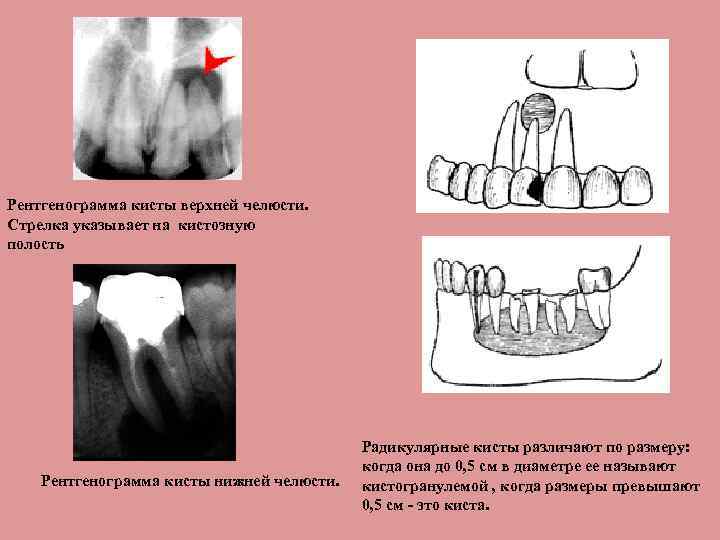

Киста Верхней Челюсти Фото

Киста Верхней Челюсти Фото 83 фотографий